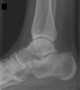

Calcaneal spur

A calcaneal spur (also known as a heel spur) is a bony outgrowth from the calcaneal tuberosity (heel bone). Calcaneal spurs are typically detected by x-ray examination. [Source: Wikipedia ]